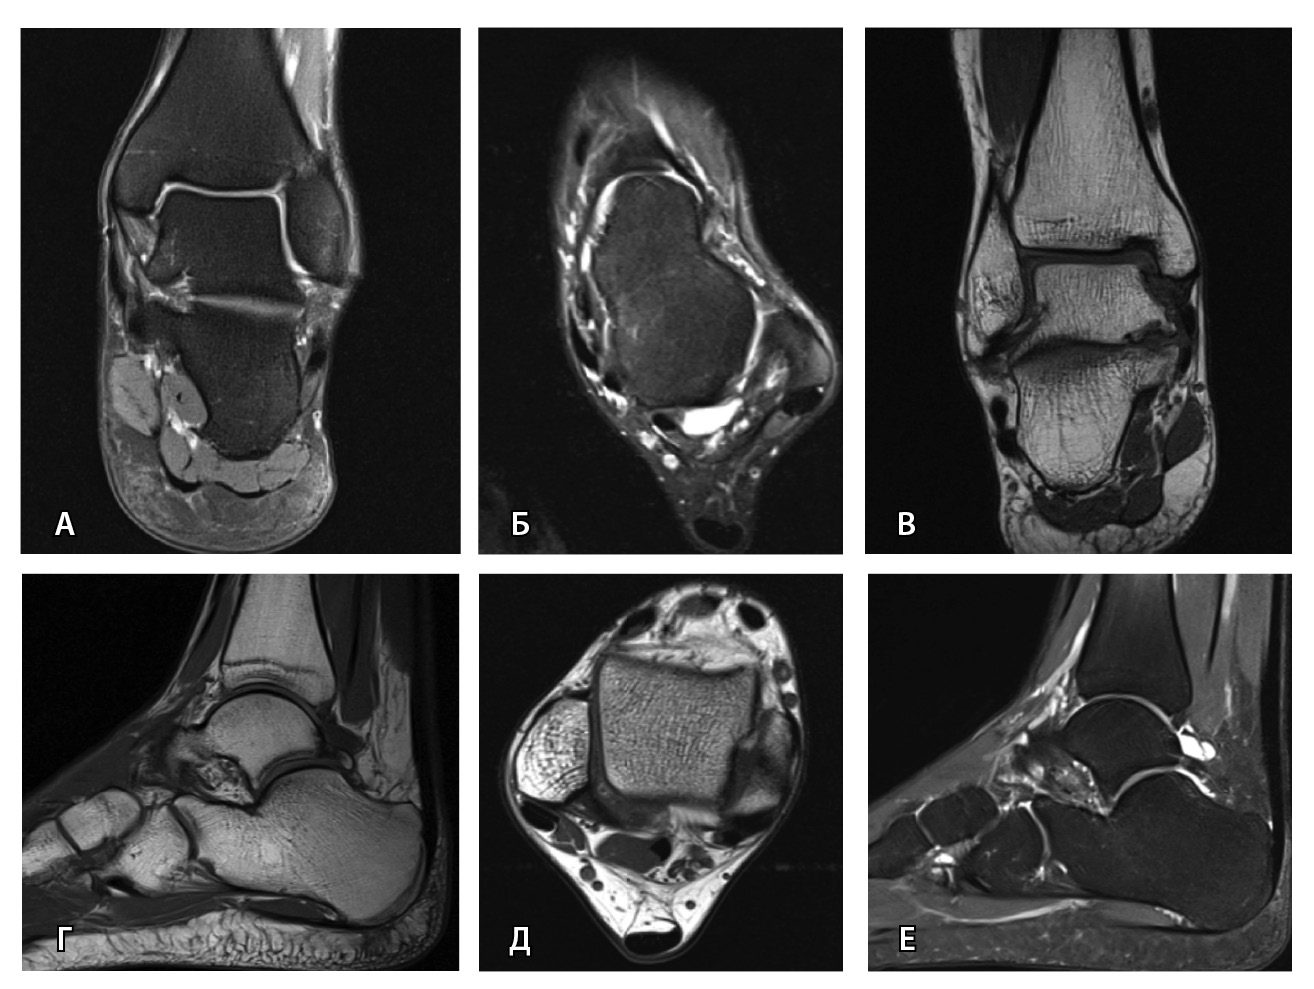

Важным условием для получения информативных МРТ-изображений является правильная укладка пациента и соблюдение стандарта сканирования: различия в натяжении или слабости связок при подошвенном или тыльном сгибании могут влиять на интерпретацию и приводить к ложноположительным или ложноотрицательным результатам [39, 52]. Магнитно-резонансное исследование выполняется лежа на спине с нейтральным положением голеностопного сустава и стопы. Рекомендации Европейского сообщества мышечно-скелетных рентгенологов 2016 г. (англ. European Society of Musculoskeletal Radiology, ESSR, 2016) по стандартному протоколу сканирования голеностопного сустава и костей предплюсны приведены в табл. 3 и на рис. 5 [56].

Рис. 5. Стандартный протокол магнитно-резонансной томографии голеностопного сустава согласно рекомендациям ESSR (2016): А – COR FS, Б – AX FS, В – COR T1, Г – SAG T1, Д – AX PD, Е – SAG STIR; AX – аксиальная, COR – корональная, FS – жироподавление, PD – протонная плотность, SAG – сагиттальная, STIR – инверсия-восстановление спинового эха